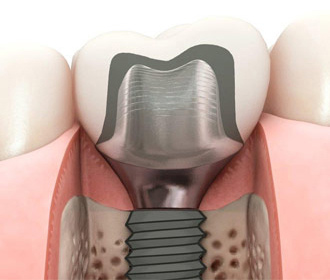

アトランティスアバットメントは、主要インプラントシステムに対する、セメント固定式およびスクリュー固定式ソリューションをサポートして、高い機能性と審美性をご提案いたします。

なぜアトランティスアバットメントを選択するべきなのでしょうか。それは、アトランティスアバットメントが、優れた補綴ソリューションに必要なデザインパラメーターを考慮しているからです。アトランティスアバットメントは、特許を取得したアトランティスVAD(バーチャルアバットメントデザイン)ソフトウェア上で、個別の欠損スペース、周囲の歯や軟組織形態を考慮して、最終歯牙形態をもとにデザインされています。これらの要素を考慮することで、出来あがったインプラント補綴物は天然歯の機能と外観を再現します。

当医院では、アストラインプラント、ZimVieインプラント、Straumannに対応しており、今までの安価なサードパーティー製のものとは一線を画する適合精度、機能性、審美性、破損時の独自の保証システムに基づいて採用しており、良好な臨床実績、成績を得ています。全ての歯牙を失った方でも、全てをインプラント治療で、元々あったご自身の歯牙と全く同じ機能、審美回復できるケース、現在、総入れ歯をご使用中で、その入れ歯にご不満をお持ちの方も、数本のインプラントと入れ歯を組み合わせる治療(インプラントオーバーデンチャー)で格段に機能回復可能なケース、さらに、ブリッジのように歯牙を削らず、単独で処置するケースなど、多彩に応用可能です。